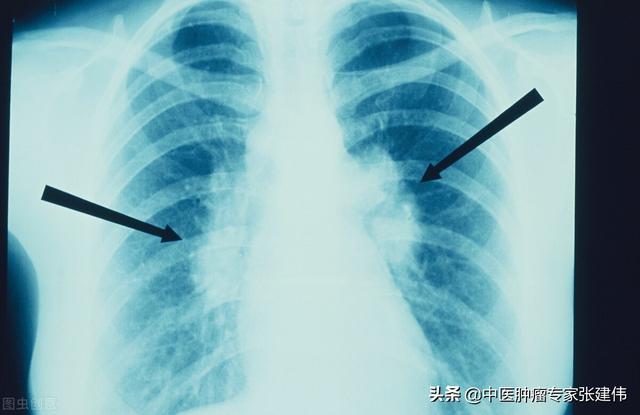

健康診断への意識が高まるにつれ、肺結節が発見される人が増えている。肺結節とは画像診断の用語で、肺結節の画像上の定義は、肺実質に完全に囲まれた、境界明瞭な小さな病変(直径≤30mm).結節の形態は、固結または亜固結に分類される。亜固結はさらに、純粋なすりガラス結節と部分的な固結に分類される。直径30mmを超える病変は結節ではなく腫瘤であり、悪性の可能性が高い。

結節の直径は悪性腫瘍の独立した予測因子であることが研究で示されている。結節の直径が大きいほど悪性腫瘍のリスクは高く、以下の確率がある:結節の直径<5mm:<1%;结节直径为5-9mm:2%-6%;结节直径为8-20mm:18%;结节直径>20mm:>50%。

肺結節:肺の組織に現れる病変である。直径30mm以下の円形または不規則な病変で、正常な肺組織に囲まれていることが多い。医用画像では「肺の高密度陰影」と表現される。肺小結節は単結節または多結節で、境界が明瞭なものと不明瞭なものがある。